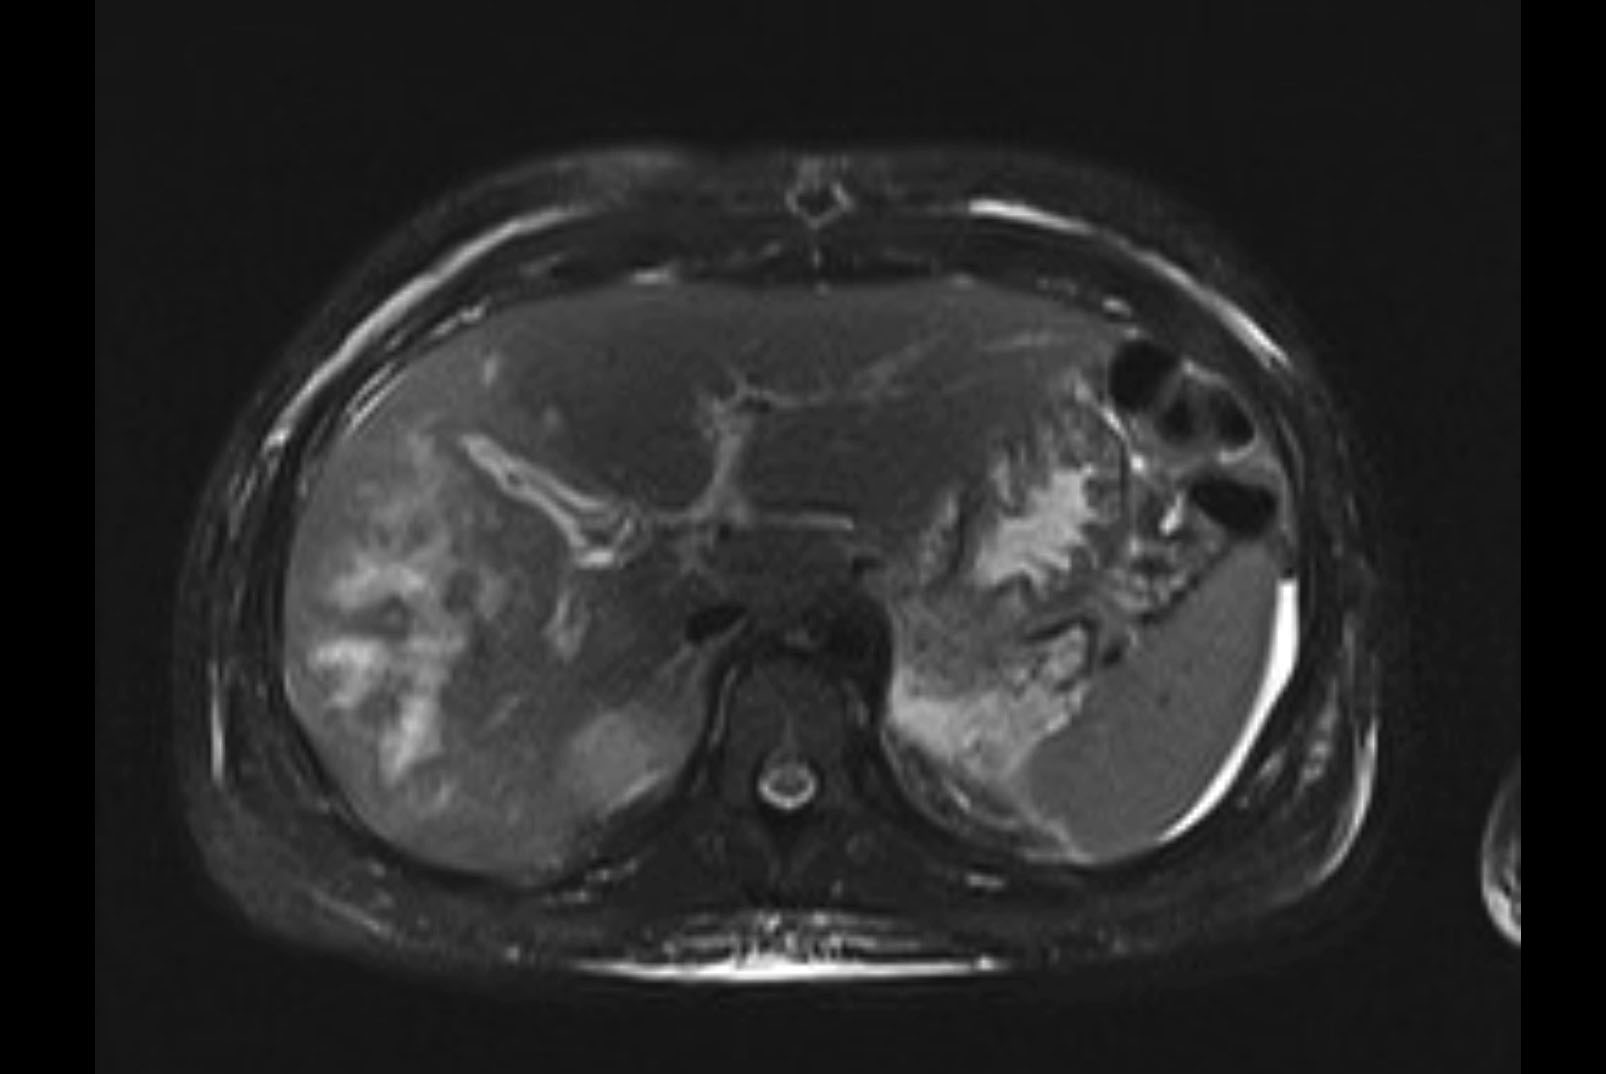

Imaging Analysis

Look through the patient's CT scan to identify any areas of concern for the necessary procedure.

MRI T1

MRI T2

Based on initial findings, which issue(s) would you be most concerned about?